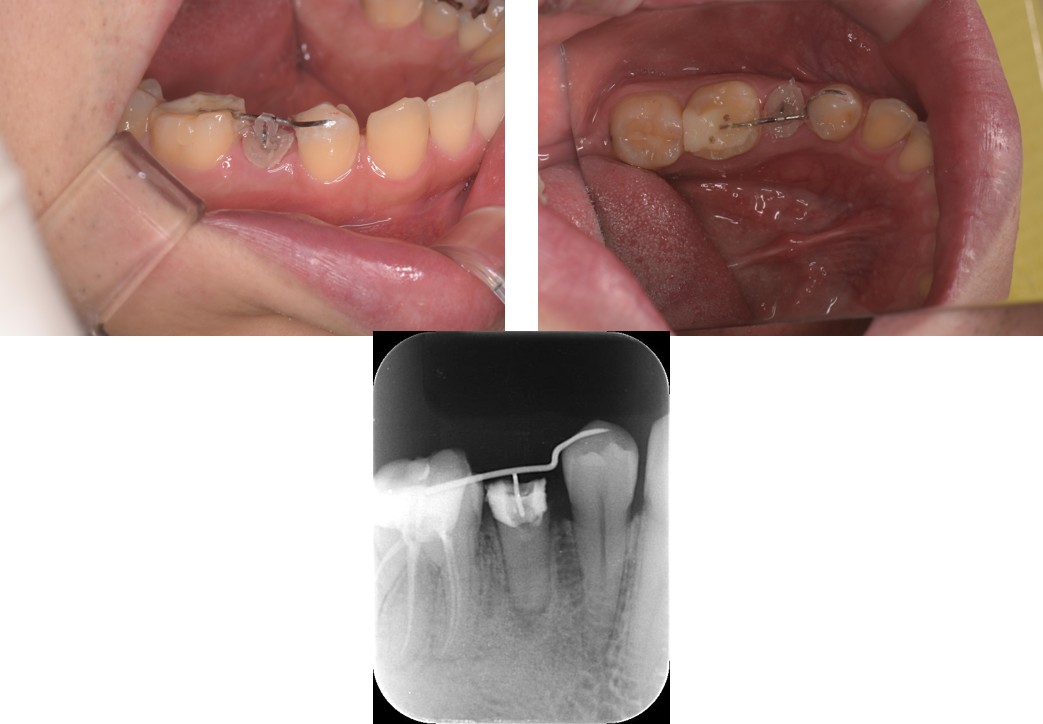

治療中の写真

まず対象の歯にフックを装着し、両隣の歯に橋渡ししたワイヤーなどを支点にして、ゴムやスプリングの力で歯をゆっくりと上方へ引き上げていきます。 |

装置をつけている間は、お口の中に少し違和感があったり、装置の周りに汚れが溜まりやすくなったりと、患者様にご協力をお願いする場面も増えてしまいます。 |